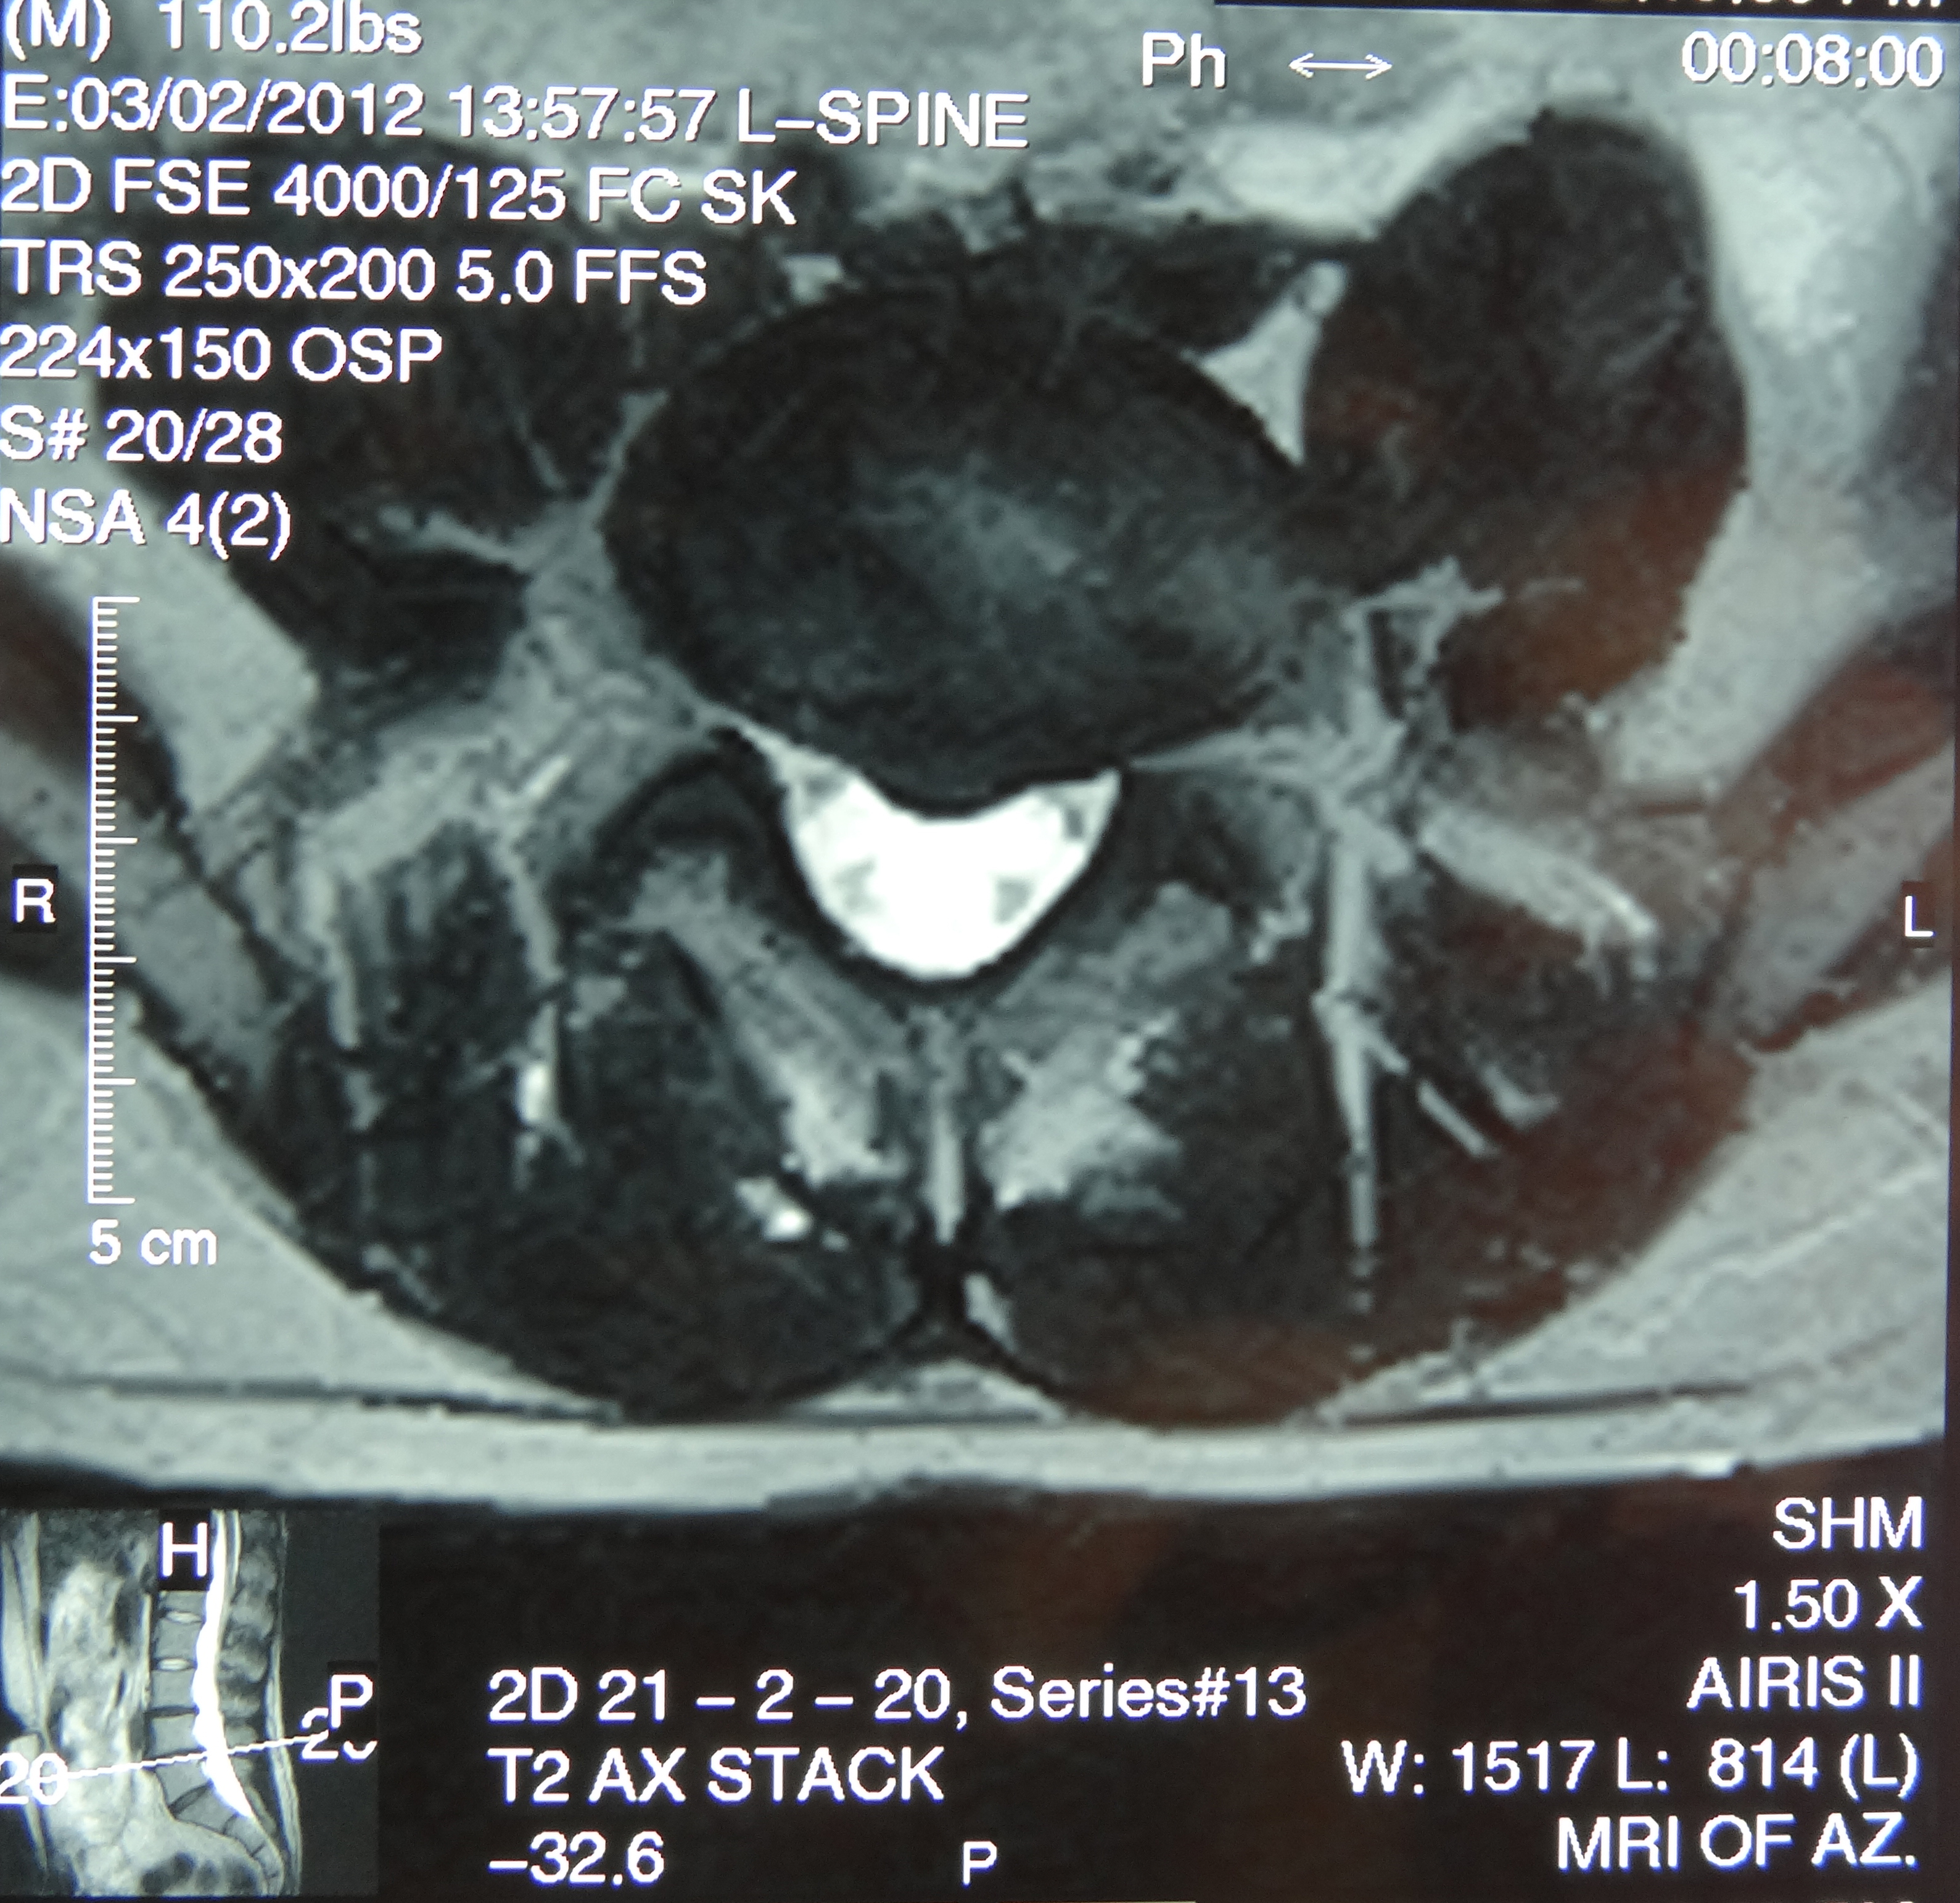

March 2019 MRI

IMPRESSION:

- Complete rupture proximal third anterior cruciate ligament with pivot shift

pattern of bone injuries lateral compartment and contrecoup bone contusion

medial tibial plateau. Joint hemarthrosis. - Complex tear lateral meniscus with inferiorly flipped flap tear extending

into the popliteal hiatus. - Complex tear medial meniscus with outwardly extruded tears of the posterior

horn and body. - Low-grade sprains medial collateral ligament and medial posterior oblique

ligament. - Low-grade sprains fibular collateral ligament and anterolateral ligament.

Intermediate to high-grade sprain popliteofibular ligament and arcuate ligament. - Grade 1 strains vastus lateralis, short head biceps, sartorius, soleus,

popliteus and anterior compartment muscles.